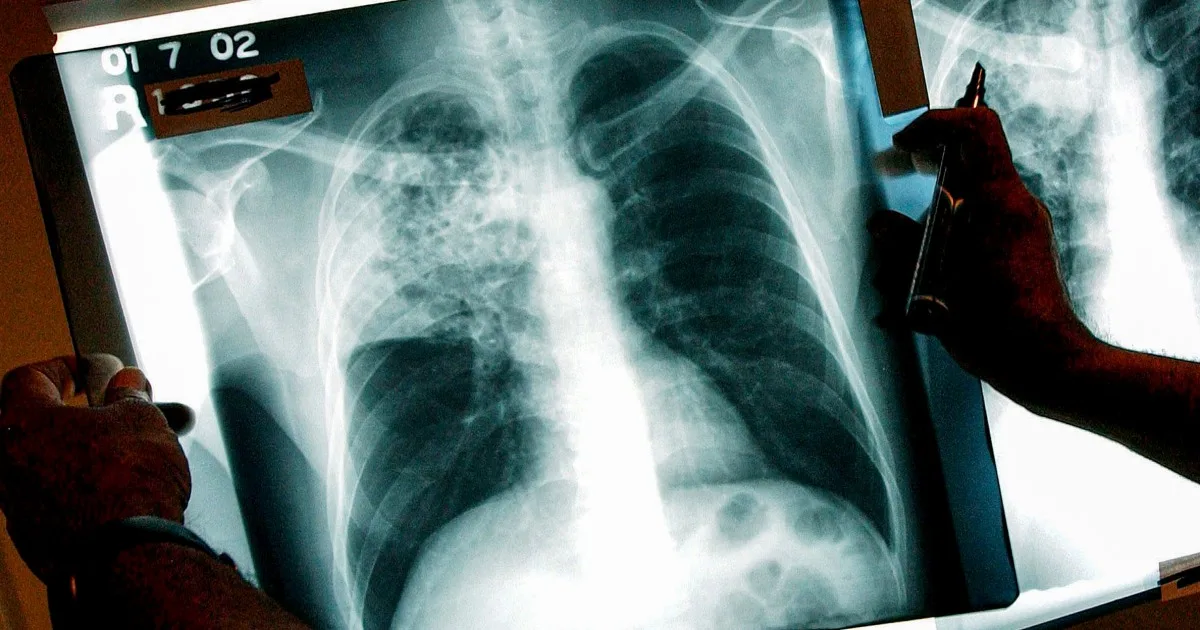

Tuberculosis is an airborne bacterial infection that mainly affects the lungs. Those sickened can have chest pain, feel weak and cough up blood or mucus from the respiratory tract, according to the CDC.